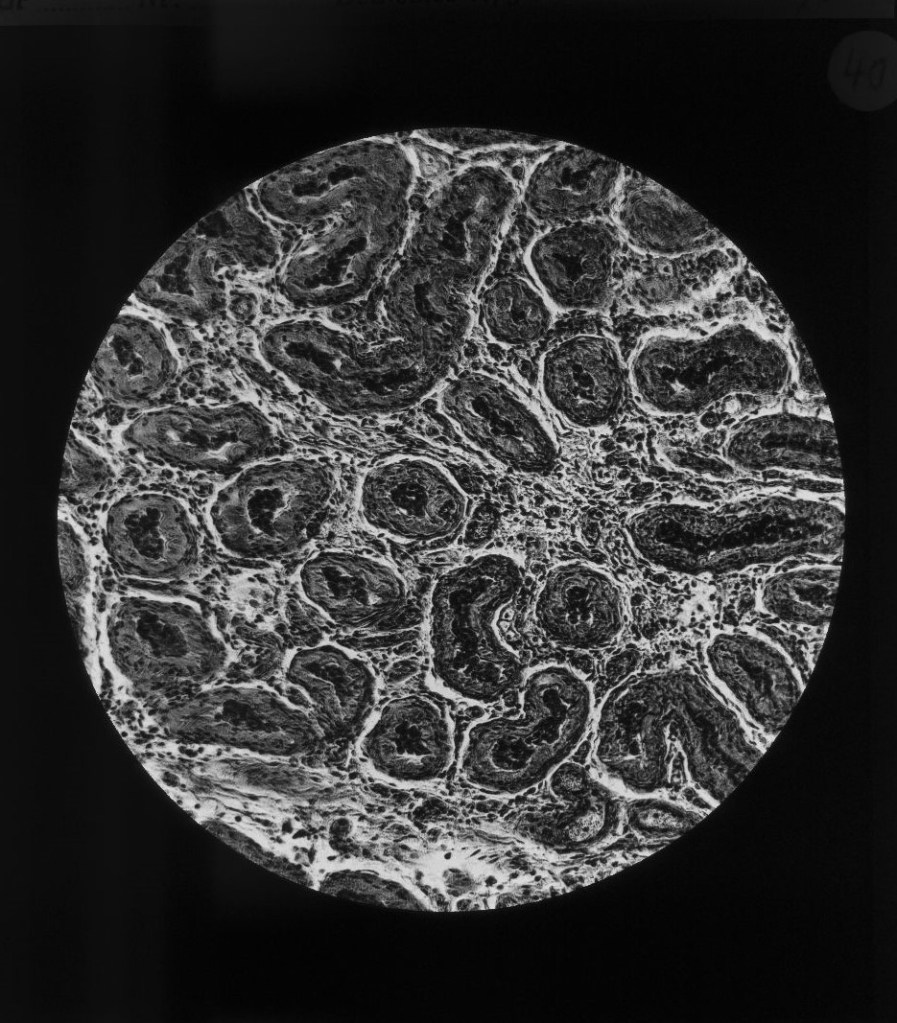

Auch mikroskopische Darstellungen wurden gezielt eingesetzt, um naturwissenschaftliche Erkenntnisse und medizinische Theorien über die Gefahren des Alkoholkonsums für die Allgemeinheit sichtbar zu machen.

Geschrumpfte Hodenkanälchen, „Degeneration“ und „entartete“ Nachkommenschaft

Gustav von Bunge (1844–1920), Basler Physiologe und ein prominenter Vertreter der wissenschaftlich geführten Abstinenzbewegung, postulierte, ausgehend vom degenerationstheoretischen Gedanken, dass der weit verbreitete Alkoholismus nicht nur den trinkenden Individuen schade, sondern eine Bedrohung der Gesellschaft darstelle, die in einer „Degeneration“ des „Volkes“ münden würde. Man bekämpfte also nicht den individuellen Alkoholismus, sondern die kollektive „Volkskrankheit“. Alkoholiker wurden so als „minderwertige“ Menschen denunziert, die mit ihrem „entarteten“ Erbgut den „Volkskörper“ schwächen. Medizinisch-mikroskopische Darstellungen liefern dafür den Beleg.

Querschnitt durch Hoden

Querschnitt durch Hoden bei einem 20järigen Trinker. (nach einem mikr. Originalpräparat von Prof. Weichselbaum). Keimgewebe entartet, zwischen den geschrumpften Hodenkanälchen massenhaft Bindegewebe.